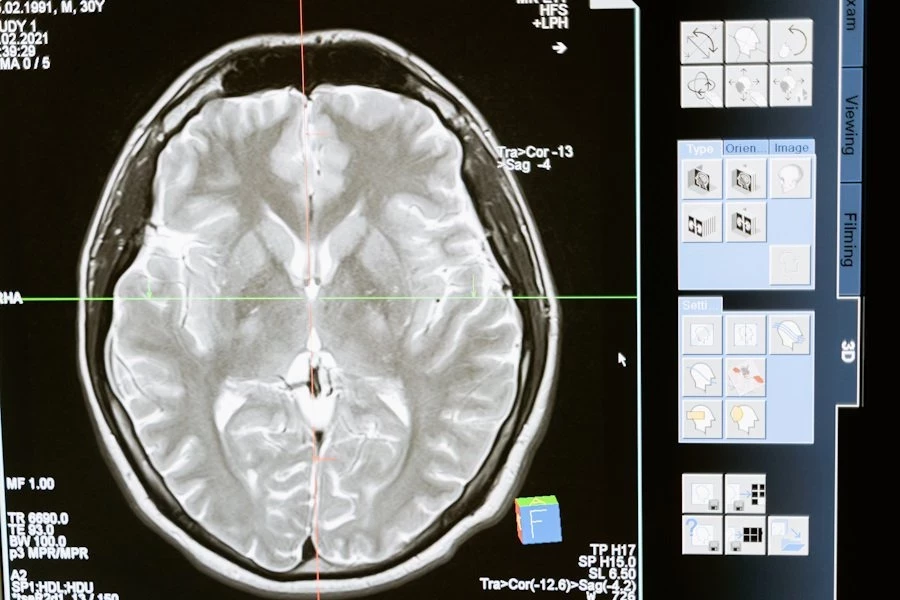

В эксперименте приняли участие 30 здоровых добровольцев обоих полов в возрасте от 22 до 40 лет. Испытуемым вводили изофлуран — популярный ингаляционный анестетик, используемый во всем мире. Ученые следили за изменениями мозговой активности с помощью электроэнцефалографии (ЭЭГ), фиксируя показатели как во время действия наркоза, так и после его завершения.